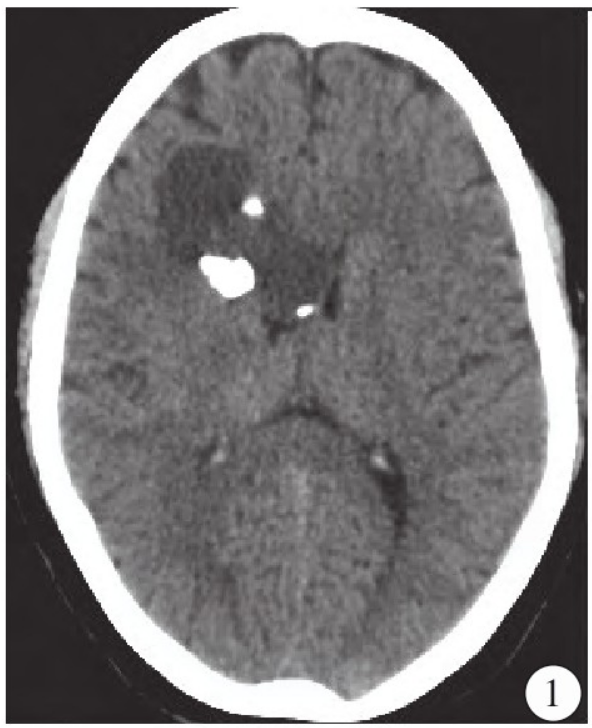

就诊。影像学检查:CT平扫

显示右侧额部直径约5.6 cm不规则混杂密度团块影,以稍低密度为主,边缘见不规则结节及斑点状钙化影,病灶深达右侧脑室旁并与侧脑室额角分界不清,右侧脑室额角受压(图1)。

图1 CT平扫显示右侧额叶及侧脑室旁最大直径约5.6cm不规则混杂密度团块影,病灶以稍低密度为主,边缘见不规则结节及斑点状钙化。